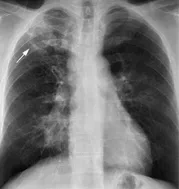

- 흉부 X선 검사 : 폐에 염증이나 병변이 있는지 확인